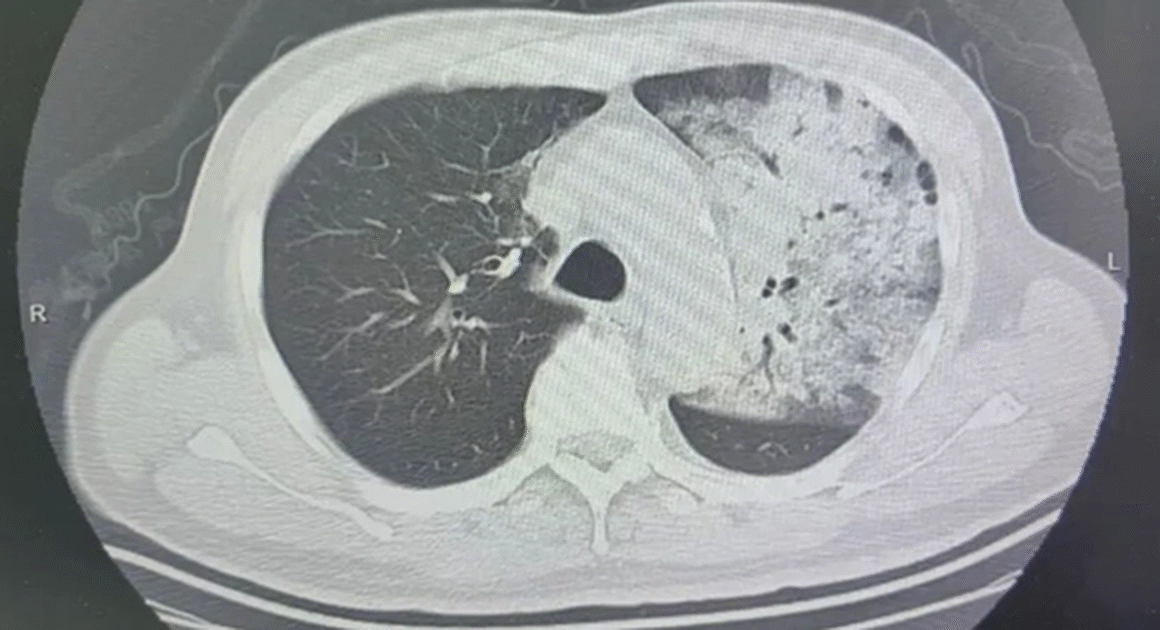

BỆNH VIỆM NGHIÊM TRỌNG TỪ ĐIỀU HÒA – AI CŨNG NÊN BIẾT ĐỂ TRÁNH TIÊU CỰC Gần đây, tại Bệnh viện Thái Châu (Chiết Giang, Trung Quốc), một bệnh nhân nam 70 tuổi đã bị viêm phổi nặng do nhiễm vi khuẩn Legionella pneumophila. Nguyên nhân chính được xác định là từ việc sử dụng […]